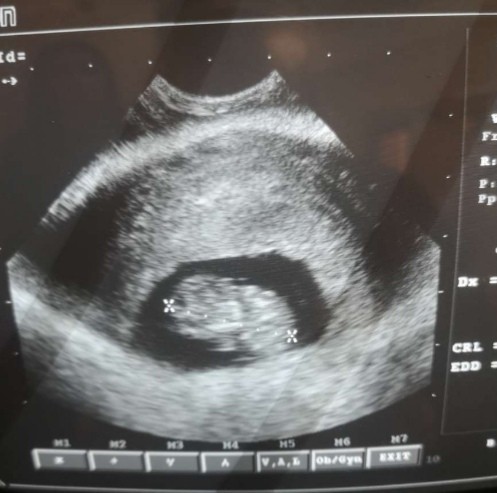

Czy ktoś może rozszyfrować to zdjęcie? Byłam na usg i ginekolog powiedziała że możliwe że jestem w ciąży. Staramy się już od ponad roku i taka wiadomość byłaby naprawdę przeszczesliwa mam pcos (nie jest to jajnik) tylko jakąś ciemna plamka

• 54b1fe8d-bddf-4159-8b95-3afb2d96a960.jpg

40,2 KB · Wyświetleń: 168